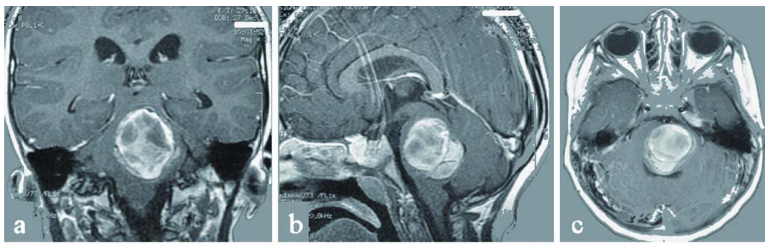

1个月时间,楠楠就从一个活泼好动的女孩变成了病床上奄奄一息的患儿。她的神经功能还在进一步恶化,而这都是由之前确诊的那个巨大桥脑海绵状血管瘤持续增大、出血,并伴有轻度脑积水导致的。

复查核磁显示,不仅原先的脑干海绵状血管瘤已生长到4×3.5×3cm,还在左额叶及顶叶也发现一个致痫病灶,同样是海绵状血管瘤。

最终,楠楠在巴教授的主刀下顺利实现病灶的全切除,手术全程进行了体感诱发电位和脑干听觉诱发电位监测,在神经导航下,桥脑海绵状血管瘤得到全切,手术过程顺利,无任何并发症。

术后,楠楠的神经症状得到持续改善。手术10天后进行的MRI检查证实海绵状血管瘤已被完全切除,并显示先前严重增大的脑干已得到减压,第四脑室恢复正常。顺利出院后,楠楠正在接受进一步的神经功能康复治疗。